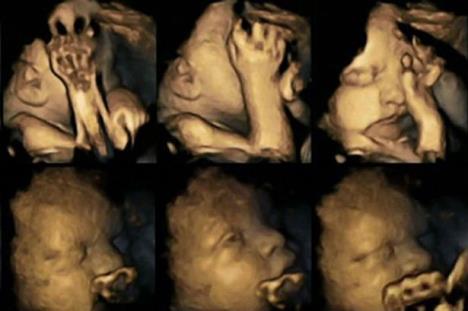

Doktorka Nađa Rajsland je 4D skenerom snimala hiljade pokreta fetusa u materici. Pratila je 20 trudnica, od čega su njih 4 pušile preko 14 cigareta dnevno

Istraživanje je napravljeno kako bi pomoglo mamama koje se muče da ostave cigarete. Doktorka Nađa Rajsland je 4D skenerom snimala hiljade pokreta fetusa u materici. Pratila je 20 trudnica, od čega su njih 4 pušile preko 14 cigareta dnevno.

Ona je nerođenu decu posmatrala u trenucima kad su bila stara 24, 28, 32 i 36 nedelja. Primetila je da su deca u stomacima trudnica koje su pušači mnogo češće pomerala usta i pipala se nego ona koja su bila u stomacima trudnica nepušača.

Fetusi u toku trudnoće dodiruju sebe sve manje i manje, do trenutka porođaja. Pogledajte kako bebe reaguju na ovu lošu naviku njihovih mama: